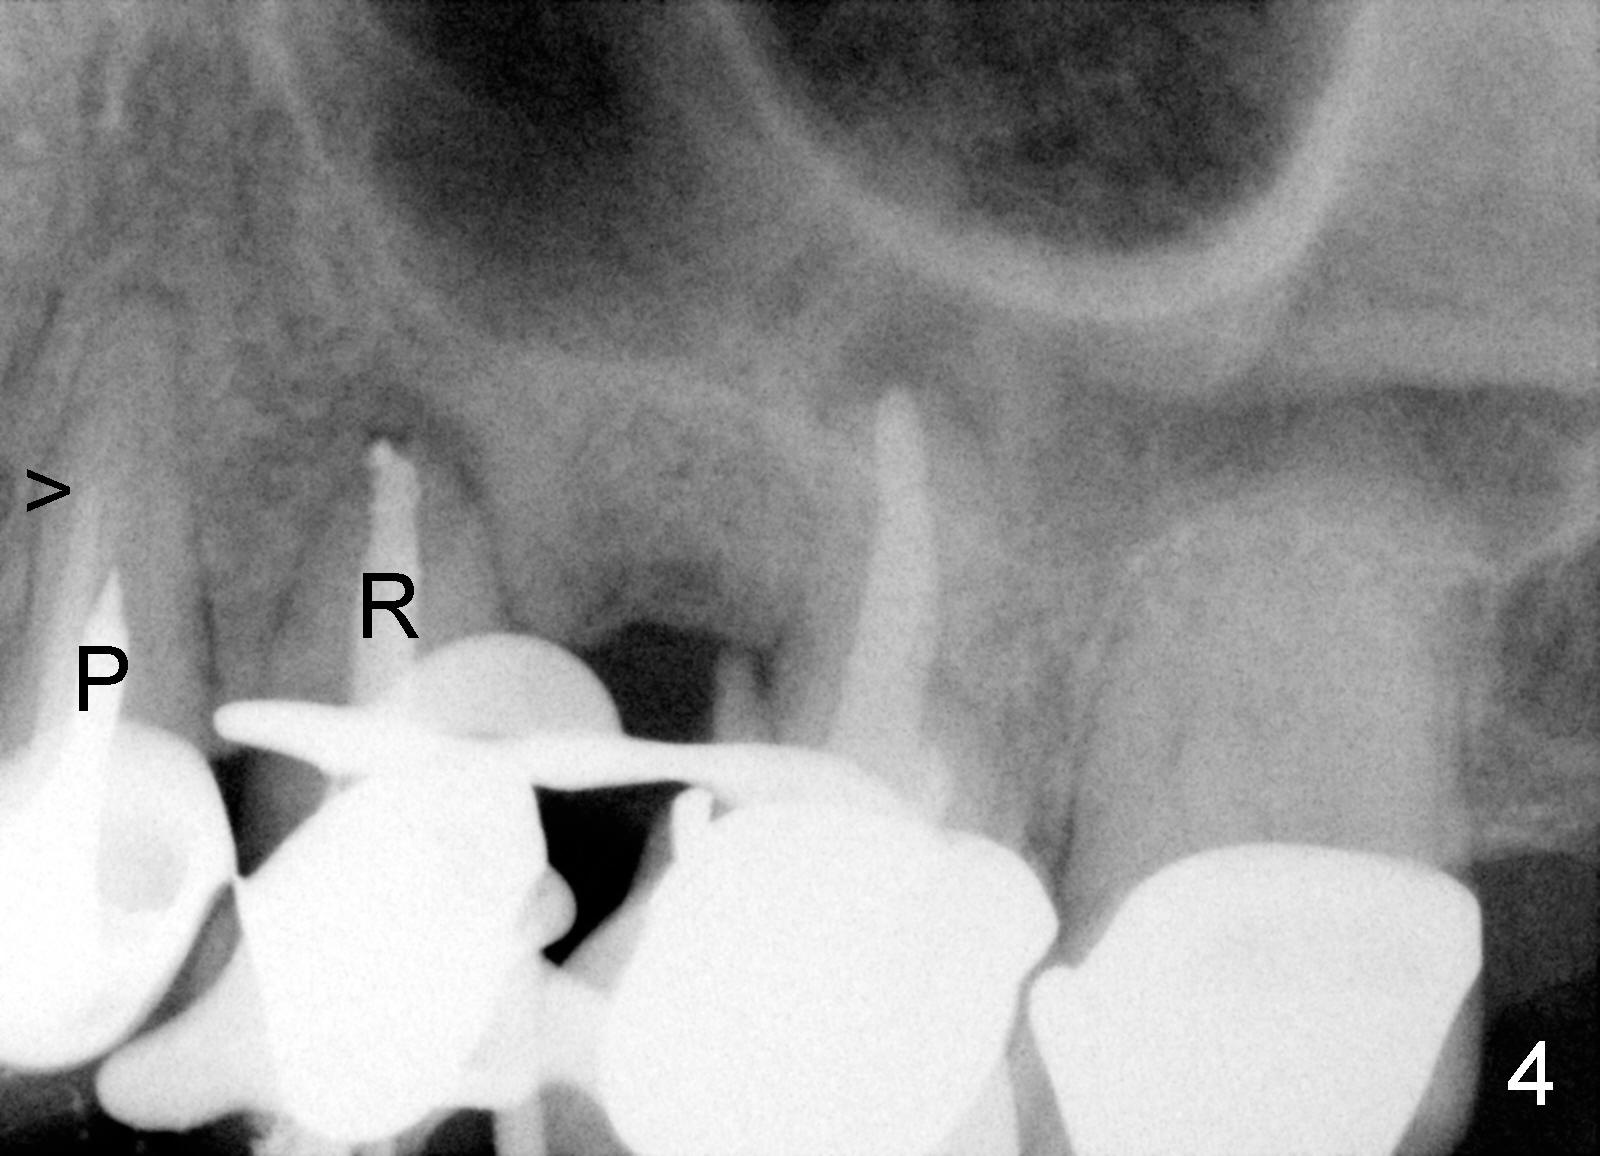

吴先生从小牙齿不好,挺能理解人,所以我们关系还能维持七八年。第一次他来时,我们诊所刚开张,没有多少病人,他左上第一磨牙近中根纵裂(图一:14**),花时间做根切(root amputation,切除近中根近中游离部分),其余两个根做根管治疗(图二)。不久以后他一直有轻微前臼齿区不适,好像第二前臼齿根管治疗充填不佳(图二<),根尖有阴影,不妨重做根管治疗(图三R),之后问题没有解决,根尖切除后,还是好好坏坏,那么再做一次根管治疗(图四R)。好不容易等到他认为疼痛来自于第一前臼齿:颊侧根充填不到位(图四箭头),鄂侧根好像有个牙桩(其实是银汞拴(Amalgam plug)),好像没有根充。这没有什么了不起:除去牙冠,牙桩,重做根管治疗,我们样样都能做。鄂侧根管很快搞通,但是颊侧根管根尖1-2 mm 阻塞,无可奈何。根充(30/.06 for L, 55 for P)后,插入两个三号Coltene Whaledent stainless steel posts以及做牙冠。每当他回来洗牙,汇报前臼齿区仍有不适,不知那颗牙齿有毛病时,对颊侧根管处理不当深感内疚,问题真得出于那里吗?